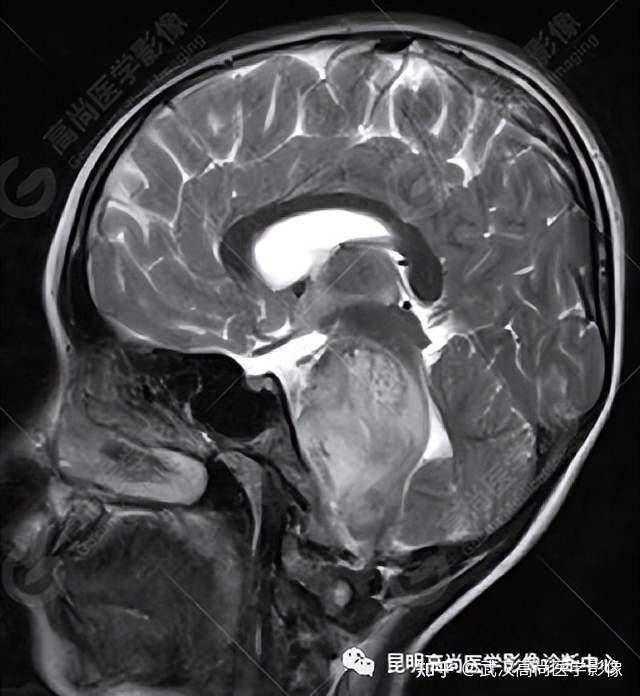

脑干弥漫性中线胶质瘤一例武汉高尚医学影像

图片尺寸640x696

矢状位可见肿瘤与脑干关系紧密.

图片尺寸1518x1486